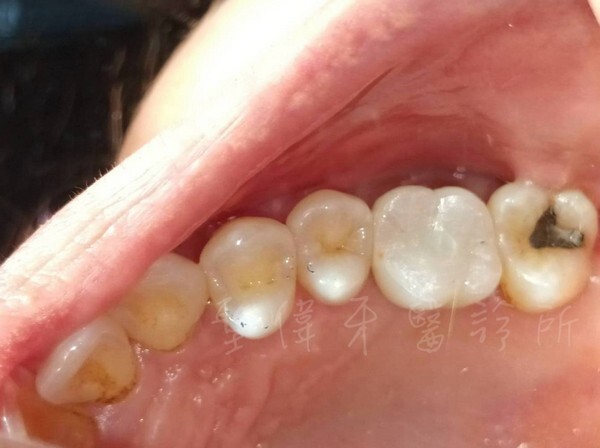

▼現在吃東西完全不會覺得不方便了

整體感覺好多了

大小跟齒面都很自然剛好

效果比我預期的更好